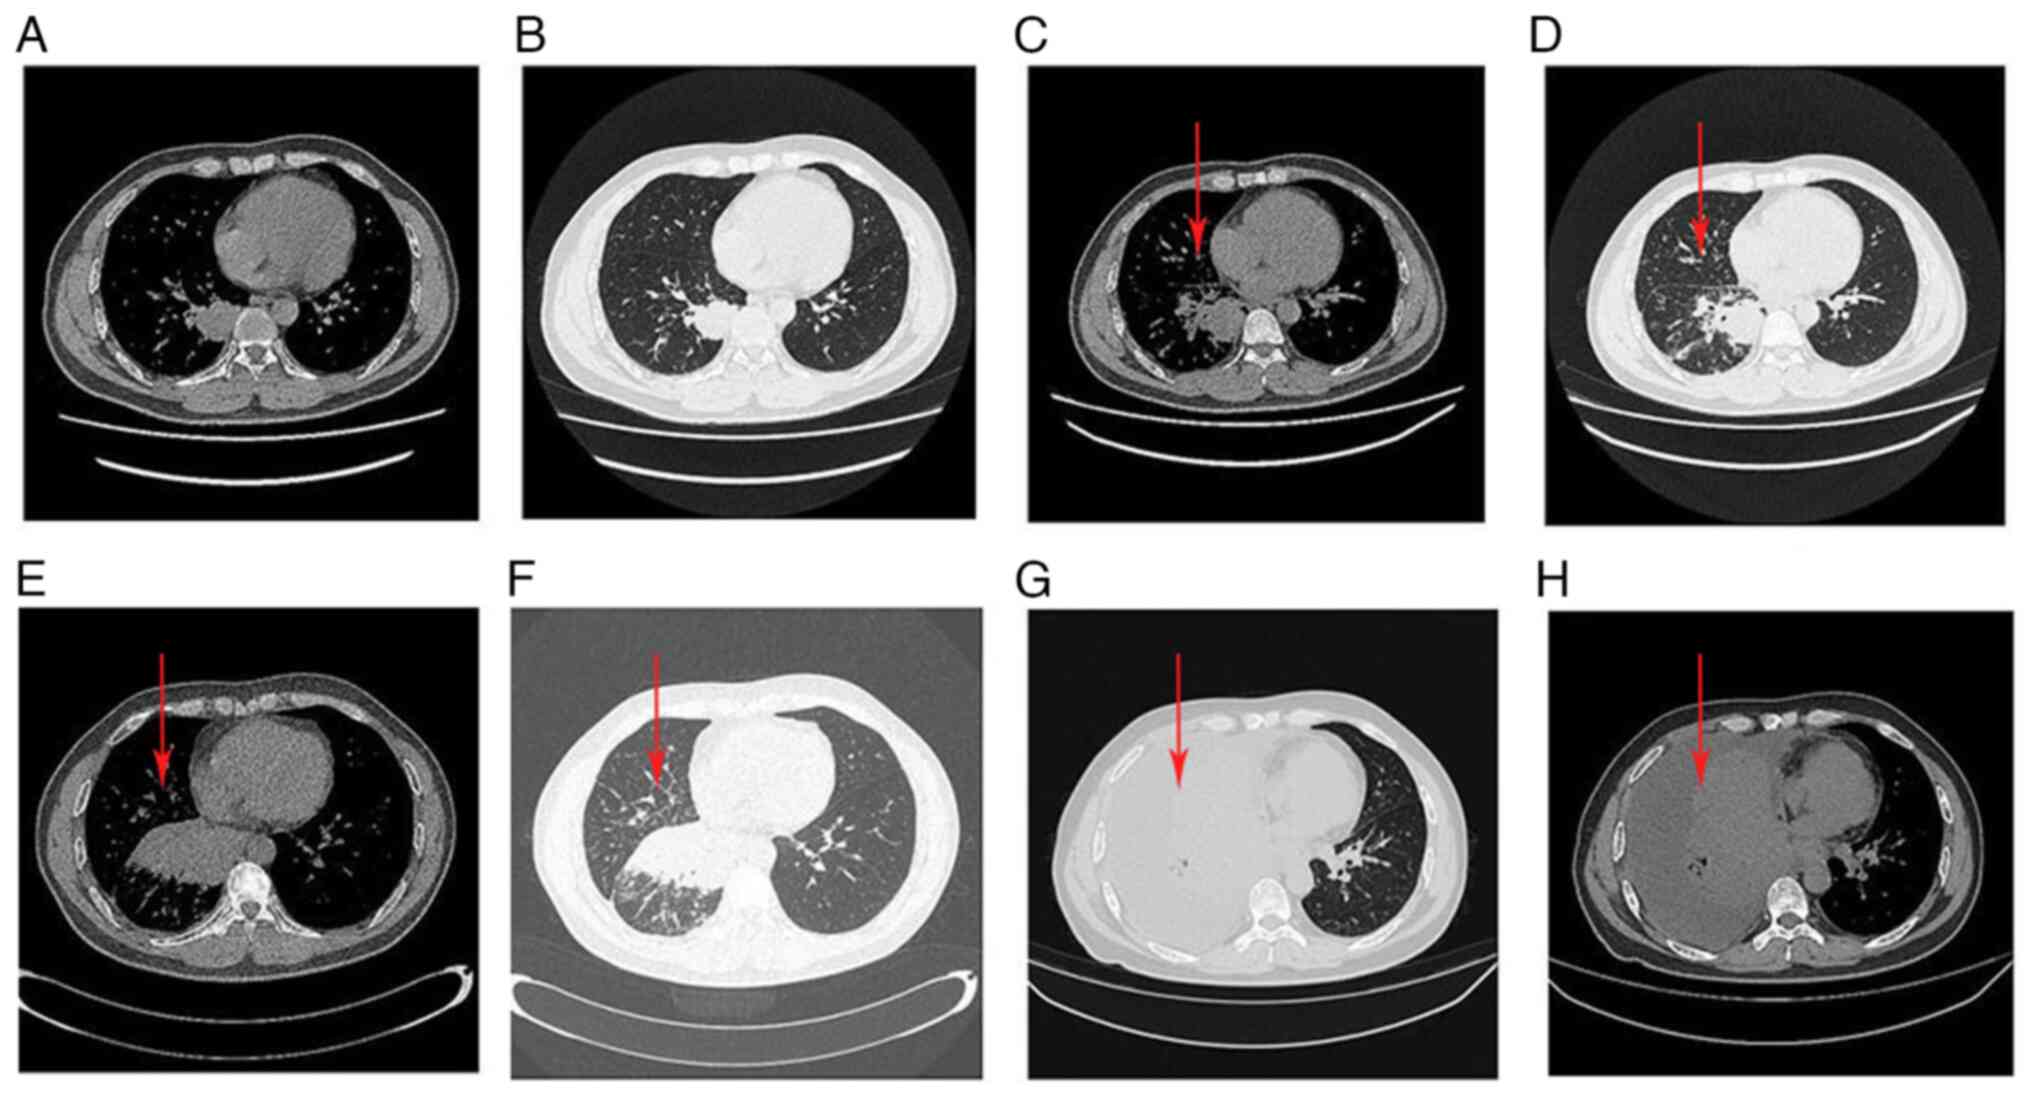

Fusion of the anaplastic lymphoma kinase (ALK) gene is a rare driver in non‑small cell lung cancer (NSCLC). Lorlatinib is a third‑generation ALK inhibitor approved for the treatment of locally advanced or metastatic ALK+ NSCLC. The traditional administration method of lorlatinib is whole tablet ingestion, while the efficacy effect of gastric tube injection after water dissolution remains unclear. In the present report, a marked response to lorlatinib in a 49‑year‑old patient with ALK+ NSCLC who was administered lorlatinib through a gastric tube, was described. The patient had received chemotherapy combined with immune checkpoint inhibitors prior to targeted drug therapy and developed hyperprogression, which was mainly manifested as rapid enlargement of the primary lesion with multiple new systemic metastases, accompanied by poor performance status score, esophageal compression and difficulty eating. The patient was injected with pre‑dissolved lorlatinib through the nasogastric tube. After 6 days, related symptoms, such as dyspnea and dysphagia, were relieved. After 18 days, the esophageal stenosis was significantly alleviated, and the gastric tube was removed. In conclusion, gastric tube injection be used as a means of lorlatinib administration in patients with ALK+ NSCLC with dysphagia, regardless of previous immunotherapy‑associated hyperprogression.

Longo V, Catino A, Montrone M, Pizzutilo P, Ugenti I, Lacalamita R, Del Bene G, Pesola F, Marech I and Galetta D: Esophageal stricture caused by ALK-positive NSCLC esophageal metastasis resolved after a few days of lorlatinib therapy without stent placement. JTO Clin Res Rep. 1:1000442020.PubMed/NCBI

Sasaki K, Yokota Y, Isojima T, Fujii M, Hasui K, Chen Y, Saito K, Takahata T, Kindaichi S and Sato A: Enteral lorlatinib after alectinib as a treatment option in anaplastic lymphoma kinase-positive non-small cell lung cancer with triple problems: Carcinomatous meningitis, poor performance status, and dysphagia-a case report. Respirol Case Rep. 9:e007962021. View Article : Google Scholar : PubMed/NCBI